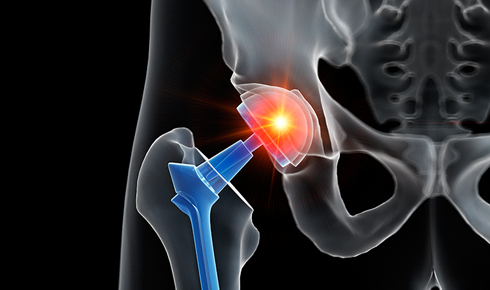

치료는 병의 원인과 심한 정도에 따라 달라집니다. 수술이 필요할 만큼 진행된 상태가 아니라면 보존적 치료를 우선하며, 약물 치료(소염진통제 등), 물리치료, 적절한 운동 처방이 기본입니다. 경우에 따라 프롤로테라피(Prolotherapy)처럼 주변 인대와 근육의 강화를 유도하는 주사 치료를 시행해 통증 완화와 안정성 회복을 도모하기도 합니다.

수술적 치료가 필요한 상황에서는 관절 내시경 수술이나 인공관절 치환술 등으로 기능 회복을 목표로 합니다. 치료 후에는 재발 방지와 기능 유지 차원에서 체중 관리, 올바른 자세 습관, 적절한 근력 운동을 병행하는 것이 중요합니다.